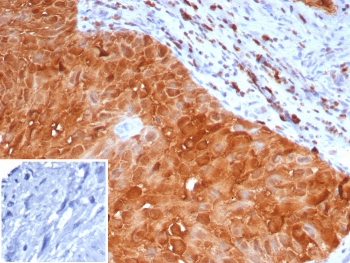

Cathepsin D Antibody

| Catalog Number | orb621663 |

|---|---|

| Category | Antibodies |

| Description | Cathepsin D Antibody |

| Species/Host | Rabbit |

| Clonality | Recombinant |

| Tested applications | FC, ICC, IHC, IP, WB |

| Reactivity | Human, Mouse |

| Antibody Type | Primary Antibody |

| Conjugation | Unconjugated |

| UniProt ID | P07339 |